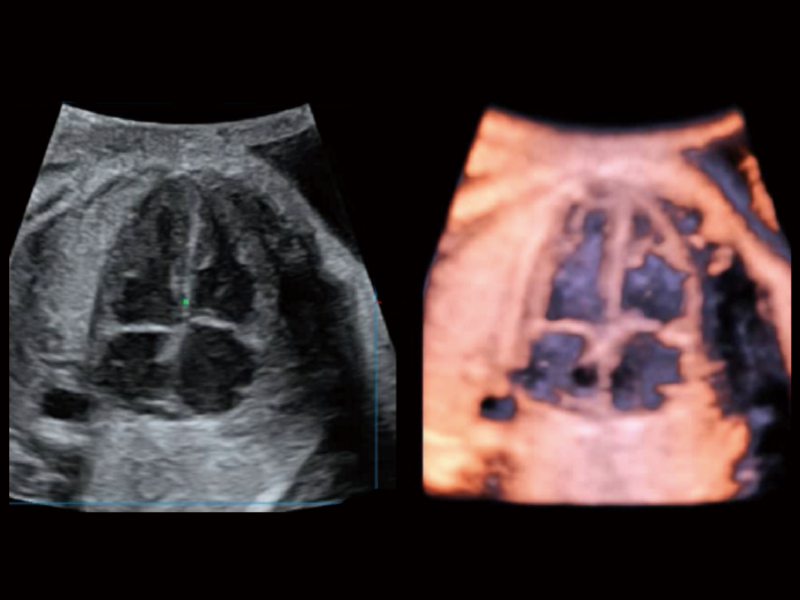

作为开立医疗全新打造的超高端旗舰超声产品,从探头抬起唤醒开启扫查到多维探头发射接收,通过先进的场成像发射、自适应聚合重建等技术,基于RF Data原始射频数据在图像生成、高端功能等方面实现突破,为妇产科、儿科提供全方位临床解决方案。

梦溪®P80以“关爱女性”为基石,提供全方位的解决方案,量身定制以满足女性的健康需求,涵盖妇科、生殖健康检查、产前筛查及产后康复等领域。